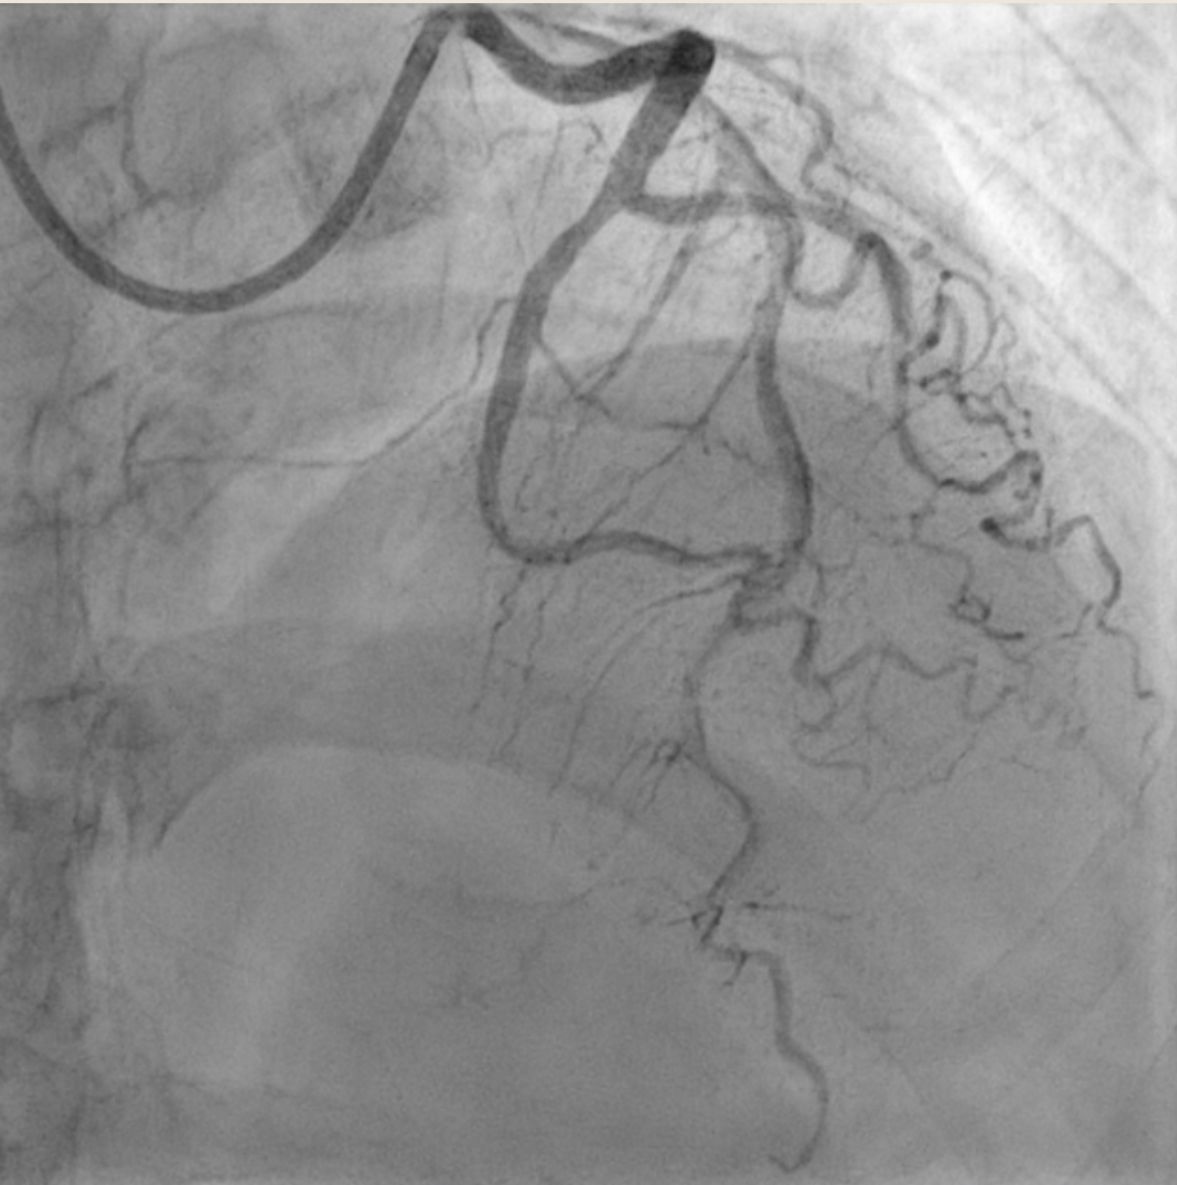

PCI was conducted using guide catheter EBU3.5/6F, A 0.014-inch floppy guidewire and was placed in distal LAD. After sliding the distal lesion with semicompliant 1.5 x 15mm, we encountered distal perforation type V with Ellis type III. Multiple prolonged ballon inflation was done using semicompliant 2.0 x 15mm at 4 atm but the perforation jet persisted. We decided to do microcatheter-assisted absorbable suture embolization technique with chromic catgut 3.0. The perforation was successfully managed. Echocardiography evaluation revealed Concentric Left Ventricular Hyperthrophy with normal LVEF without signs of pericardial effusion. Patient was dismissed from hospitalization without further complication.

We reported a 56-year-old female with NSTEMI and PCI was done with Type V coronary complication and successfully sealed with Chromic Catgut suture embolization. the use of chromic gut suture for sealing Type V coronary perforations appears to be a feasible and safe bailout option when conventional methods are unsuccessful or not applicable. The technique provides targeted, distal microvascular embolization. However, its efficacy and long-term safety remain unproven. Large-scale registries or randomized trials are warranted but are challenging due to the rarity of the event.